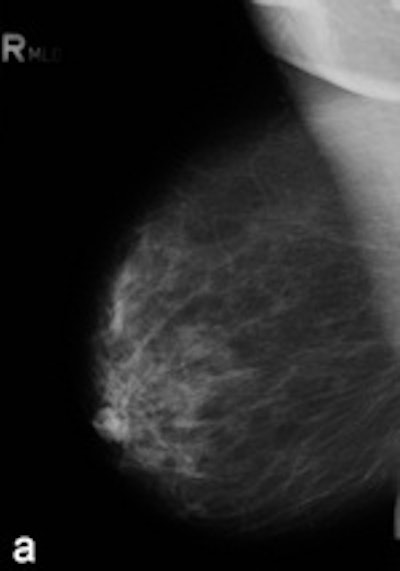

| Example of a subtle finding in a right-sided mediolateral oblique view, which was only reported by radiologists when using premium view (PV). A: Digitized prior. B: Tissue equalization (TE) processed image. C: PV processed image with the annotation. D: The resulting image of subtracting TE from PV. E: Thresholded version of D. White areas indicate that pixels in the PV image have relatively higher intensity than the related pixels in the TE image, whereas black areas indicate the opposite. In PV images, low-frequency trends are suppressed (no noticeable signal decrease in the breast edge in PV compared with TE), whereas higher-frequency structures are emphasized (e.g., glandular structures). All images courtesy of Wouter Veldkamp, PhD, Leiden University Medical Center. |

The cases were acquired using the Senographe Essential digital mammography system (GE Healthcare). Tissue equalization is a standard GE application that corrects for low-frequency variations resulting from under- and overpenetration of x-rays. As a result, the image dynamic range is reduced, enabling improved soft-copy image display.

The local contrast optimization, premium view, has been designed to improve the quality of the information presented to the radiologist for diagnosis and also the reading speed by optimizing the local contrast in breast structures. In premium view, low-frequency structures are obtained from the original image by low-pass filtering. High-frequency structures are obtained by subtracting the low-pass filtered image from the original image. The low- and high-frequency images are both processed and weighted individually, then added together. The resulting image exhibits reduced contrast between different tissue types but enhanced contrast of small-scale anatomical architecture.

Another example of a finding in a left-sided craniocaudal view that was reported clearly more often by radiologists when using premium view (PV). A: Tissue equalization (TE) processed image. B: PV processed image with the annotation. C: Similar to image above, the resulting image of subtracting TE from PV. D: The thresholded version of C.For all six radiologists, perceived case suspiciousness -- defined as the highest probability of malignancy of all radiologist findings -- was higher using premium view optimization.

The major difference between the processing algorithms was an additional local contrast optimization when premium view was applied. "Premium view is aimed at increasing the visibility and suspiciousness of malignant lesions, but in our study the perceived suspiciousness of benign lesions and normal cases is increased as well," the researchers wrote. "An effect of local contrast enhancement could be that both normal (dense) structures and abnormal structures appear more suspicious due to their enhanced signal."